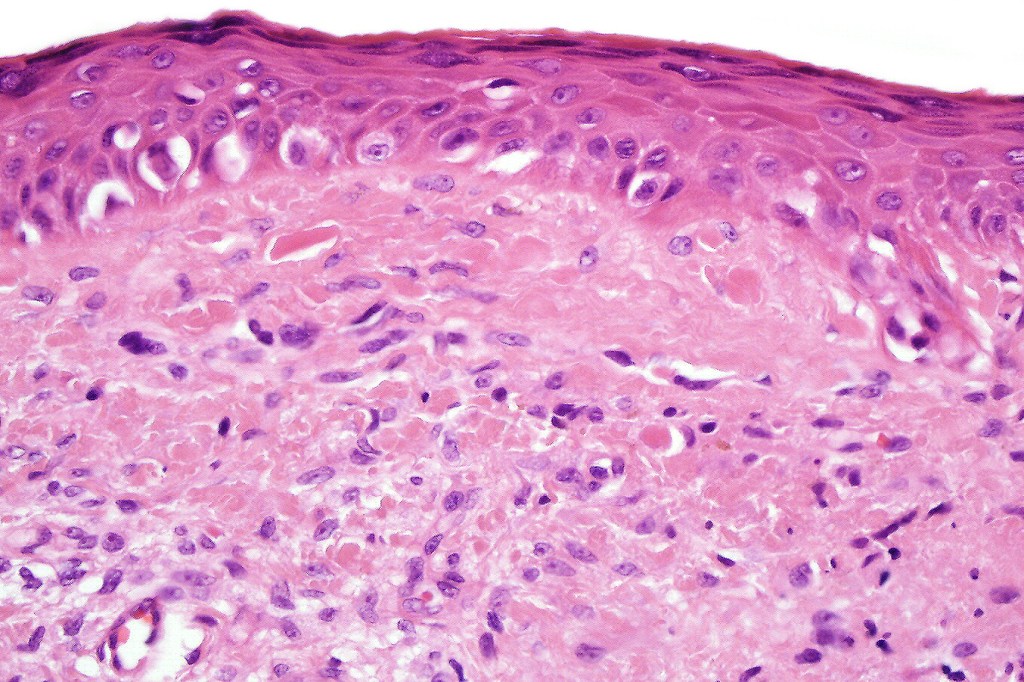

•Epidermal atrophy & solar elastosis

•Atypical melanocytes located predominantly along the basal layer of the epidermis, singly, in short arrays or extensively involving the whole epidermis

•Cytoplasmic retraction artifact, nuclear hyperchromatism with irregular borders

•Dermal melanophages & lymphocytic infiltration